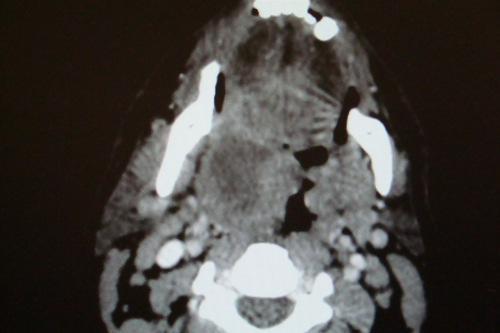

Paciente masculino, 20 anos, dá entrada no pronto-socorro, relatando odinofagia unilateral intensa, com irradiação para orelha ipsilateral, febre 39 graus, limitação à abertura bucal, voz anasalada, mas eupneico, estado geral preservado, pulsos cheios e simétricos, normotenso. Quadro com cinco dias de evolução e está em D4 de amoxicilina. Apresenta a tomografia acima.

Sobre esse relato, podemos afirmar: